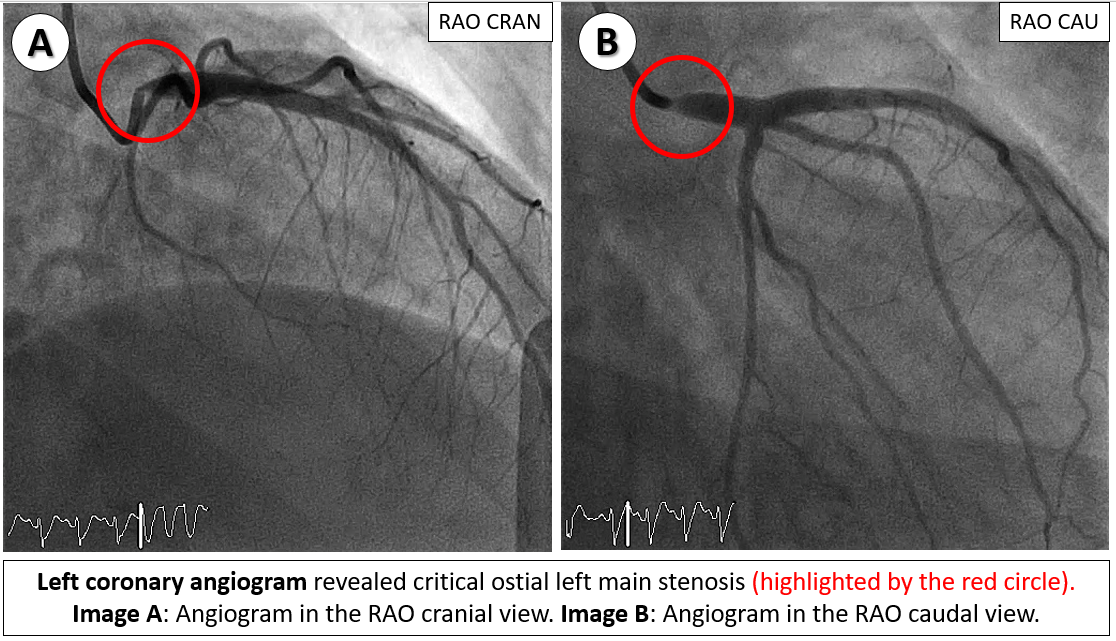

Relevant Catheterization Findings

Emergency coronary angiography revealed a critical ostial left main stenosis with TIMI 2 flow and a normal right coronary artery. Following engagement with 6-Fr JL 4.0 side-hole catheter, sequential pre-dilatation was performed using 3.5x15 mm and 4.5x15 mm non-compliance (NC) balloons. A 4.0x12 mm drug-eluting stent was deployed in the left main artery, followed by post-dilatation with a 4.5x15 mm NC balloon. Subsequently, an intra-aortic balloon pump was inserted for hemodynamic support.